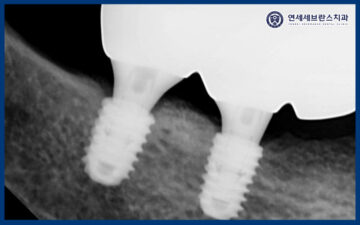

25.01.11 / 25.02.08

먼저 위쪽부터 남아있는 치아를 발치 후

임플란트 식립을 진행하였습니다.

오른쪽 위 첫 번째 큰 어금니 부위는

앞서 말씀드린 것처럼

잇몸뼈의 양이 충분하지 않은 상태였기 때문에,

상악동 측방 거상술을 통해

부족한 뼈를 보강한 후

임플란트를 식립하였습니다.

상악동거상술을 통해

임플란트가 안정적으로

자리 잡을 수 있는 충분한 공간을 확보하고,

장기적인 예후를 고려한

치료를 진행하였습니다.